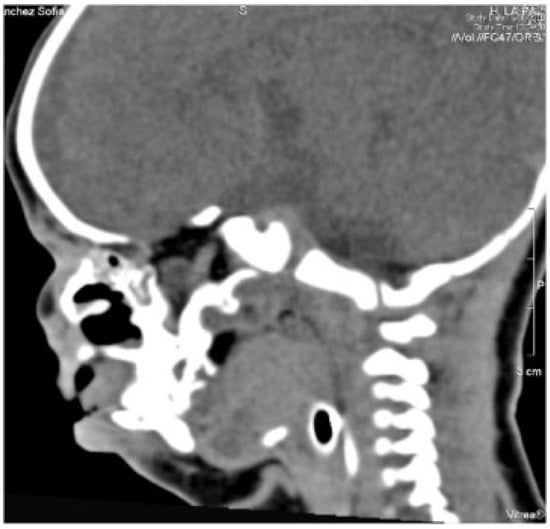

She exhibited no respiratory distress, and nasotracheal intubation or tracheotomy was unnecessary; intervention was planned 1 week later. Airway management made it necessary to perform a tracheotomy. Neurologically, she was conscious with correct muscular tone. The laboratory analysis revealed no pathology. Thorax radiology showed a double image of vertebral bodies in the cervical level. Ultrasound revealed the agenesis of corpus callosum, as suggested by the MRI. Computed tomography showed the same pathology in addition to complete frontonasal dysplasia (Figure 5). Ophthalmologic study described a severe hypertelorism with blepharophimosis. Pupillary and foveal reflexes were normal. Transparent corneas were normal in size with absence of cataracts. Abdominal ultrasonography discarded any other associated pathology. Surgical treatment was planned with a stereolithographic model when the child was 2 weeks old.

Figure 5.

Computed tomography shows the agenesis of corpus callosum.